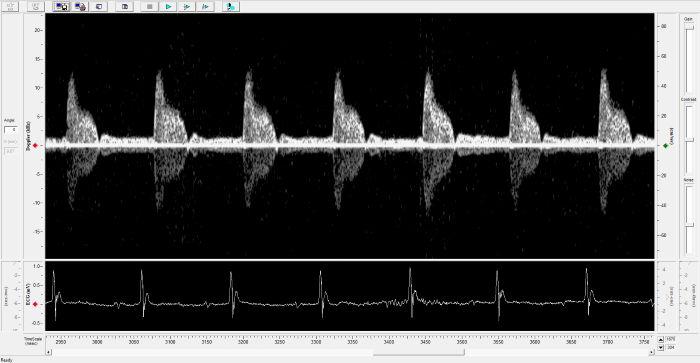

Mouse - Abdominal Aorta

Mouse - Abdominal Aorta. Image Credit: Scintica Instrumentation Inc.